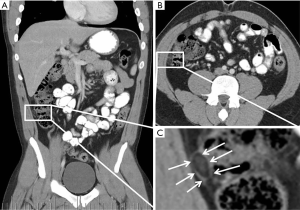

A 23-year-old male presented to the emergency department (ED) with acute right lower quadrant abdominal pain. The pain was described as achy in nature, does not radiate, and without aggravating or relieving factors. The patient reported associated nausea, but without vomiting or fever. A computed tomography (CT) scan was obtained in the ED, which demonstrated a hyperattenuating lesion along the right colon (Figure 1) compatible with epiploic appendagitis.

On CT study, acute epiploic appendagitis consists of an oval lesion with fatty tissue attenuation that is commonly 1.5–3.5 cm in diameter, but no larger than 5 cm, lying adjacent to the anterior surface of the colon wall (7). The lesion is surrounded by a hyperattenuating ring, reflective of inflammatory changes. A central high attenuation region indicating venous thrombosis is frequently visualized (7). Occasionally, inflammation will cause parietal peritoneum thickening (1,7). Acute epiploic appendagitis rarely causes colonic wall thickening or occurs in hernia sacs, although Singh et al. documented the first case within an incisional hernia sac in 2004. Although symptoms should subside within weeks, CT changes are slower to occur, but will resolve by 6 months (20-22). Ultrasound imaging at the point of maximum tenderness will demonstrate an oval non-compressible hyperechoic mass, circumscribed with a hypoechoic rim, abutting the colon wall (22-24). The color Doppler will indicate no central blood flow (24,25). Although acute epiploic appendagitis can be distinguished on ultrasound, Danse et al. recommend that ultrasounds be used only in thin patients at experienced centers. MRI shows a focal lesion with fat attenuation (26).